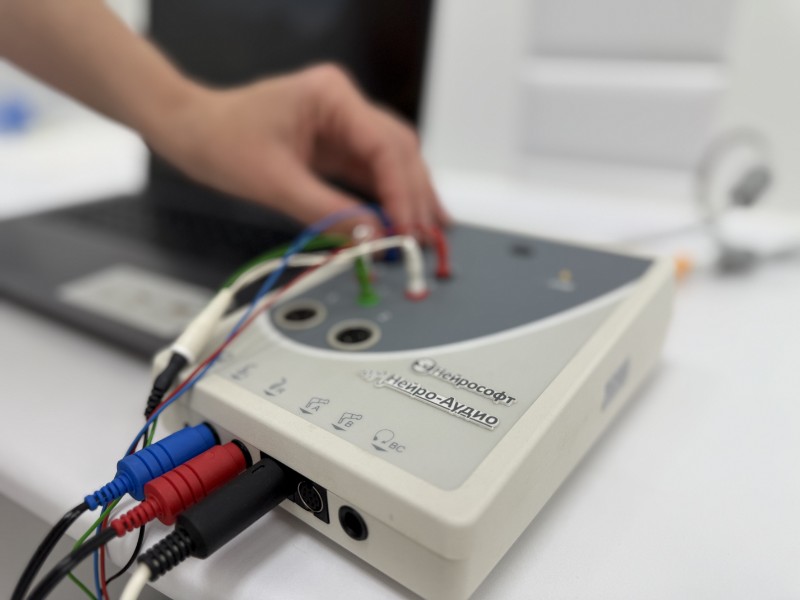

28.10.2025В сочинской «Клинике уха, горла и носа» теперь доступна комфортная диагностика слуха для детей с рождения методом КСВП.

28.10.2025В сочинской «Клинике уха, горла и носа» теперь доступна комфортная диагностика слуха для детей с рождения методом КСВП. -